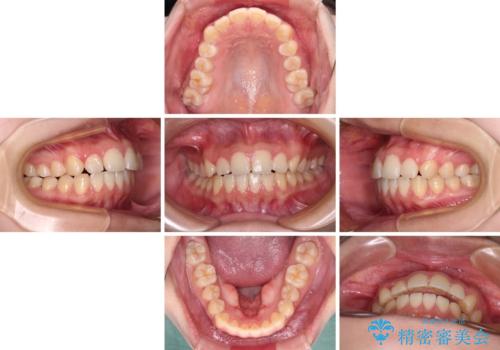

- 前歯の叢生を気にして来院された患者様です。

奥歯の咬み合わせを見ると、上顎が下顎に対して相対的に前方にあり、上下の前歯が接触していない状態でした。

咬み合わせを改善するためには、上顎臼歯を後方に移動させた咬み合わせにする必要があります。

インビザライン単体で改善することも可能ですが、咬合力が強く、単位で達成する可能性が低いと考えられたため、カリエール・ディスタライザーという補助装置を併用して、より確実性を上げることとしました。

奥歯の咬み合わせを改善しながら、並行してインビザラインで歯列を整えることとしました。